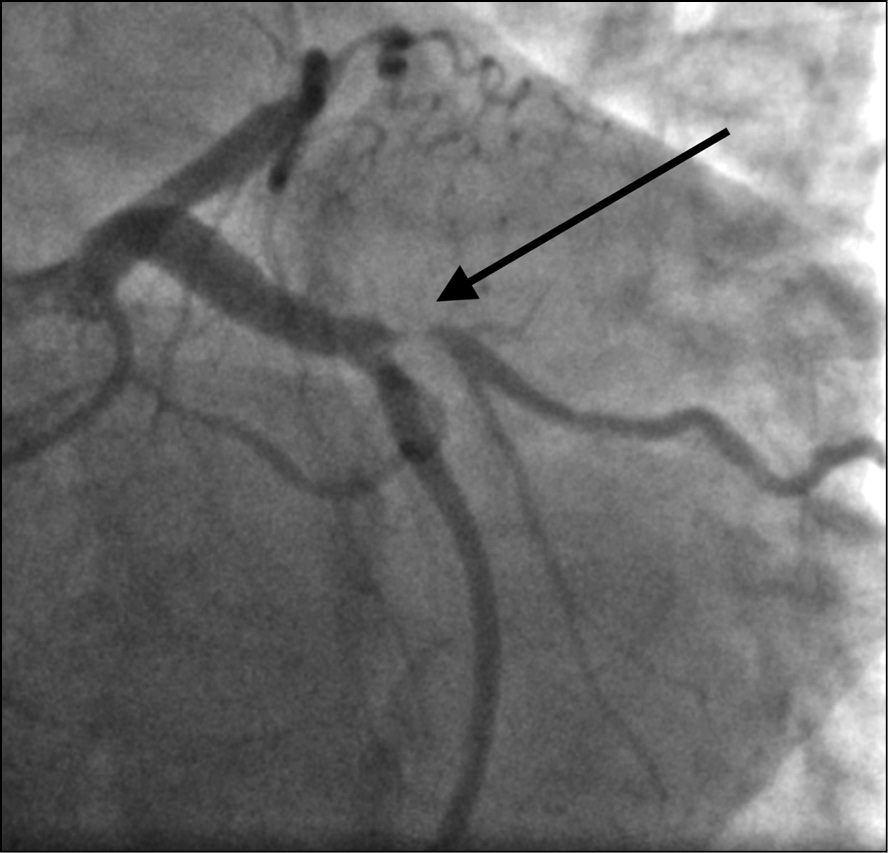

Выполнена коронарография трансрадиальным доступом, на которой выявлено многососудистое поражение коронарного русла: субокклюзия средней трети передней нисходящей артерии (рис. 2), субокклюзия устья первой ветви тупого края (рис. 3), субокклюзия проксимальной части правой коронарной артерии (рис. 4). Диаметр правой коронарной артерии менее 2 мм. Левый тип кровоснабжения миокарда. Тяжесть поражения коронарного русла по шкале Syntax 1 [3] составила 13 баллов (легкая). Рекомендованный метод реваскуляризации миокарда по шкале Syntax 2 [4] — аортокоронарное шунтирование (53,6 балла для чрескожного коронарного вмешательства и 28,6 баллов для аортокоронарного шунтирования).

Рис. 2. Пациентка Б., 64 года, с острым коронарным синдромом, находящаяся на программном гемодиализе: при коронарографии трансрадиальным доступом выявлена субокклюзия средней трети передней нисходящей артерии (указана стрелкой)